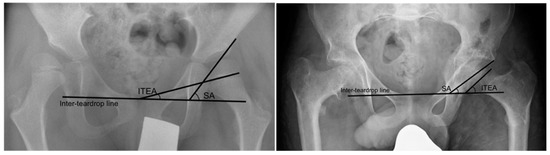

Two methods of measuring the orientation of the growth plate in relation to the acetabulum were used. The acetabular-epiphyseal angle (AEA) was measured by subtracting the Hilgenreiner epiphyseal angle (HEA) from the AI. This has previously been shown to be correlated with MP in a preliminary study [28]. We also measured the difference between the angle between the growth plate and the inter-teardrop line, and the Sharp angle [Figure 2].

Figure 2. Angles used for measuring the orientation of the femoral growth plate. (A) Angles used to measure the acetabular-epiphyseal angle. (B) Angles used to measure the difference between the inter-teardrop epiphyseal angle and Sharp angle. AI = acetabular index. HEA = Hilgenreiner epiphyseal angle. ITEA = inter-teardrop epiphyseal angle. SA = Sharp angle.

An example of the change in growth plate orientation after hip reconstruction surgery in a non-ambulatory (GMFCS IV), 7-year-old male with bilateral CP is shown in Figure 6. In the pre-operative radiograph, the femoral head deformity was classed as grade B (flattening on one side). The difference between the ITEA and SA was 39.0°. In the late post-operative radiograph at 7.5 years follow-up, the femoral head remodelled to a grade A (spherical) head, with the growth plate orientation changing such that the difference between the ITEA and SA was markedly reduced to 4.6°.